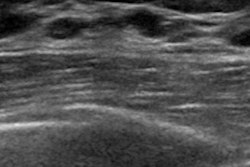

In the study, 16 subjects received injections of either the predicate agent Perflutren or CardiSon at four different dose levels prior to echocardiographic imaging, which was performed at three different time-points after injection. Three cardiologists, blinded to which agent was administered, then evaluated the images based on visualizing the borders of the left ventricle of the heart and the presence or absence of shadowing.

“CardiSon provided statistically significant better contrast enhancement on the study as well as minimal shadowing. The safety and laboratory parameters from the study indicated that both CardiSon and Perflutren were safe,” said one of the study leads, Elizabeth Krupinski, PhD, of Emory University, in a news release.

The study suggests that CardiSon will provide contrast over a wide range of doses and help avoid shadowing, which can be seen with some agents at higher doses, added the company’s founder and chief executive officer, Evan Unger, MD.